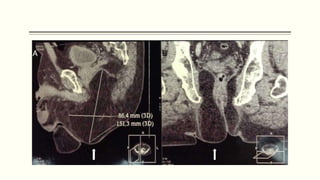

TOMOGRAFÍA COMPUTARIZADA (TAC) DEL ABDOMEN Y PELVIS

 La figura muestra una imagen de

TAC abdominal simple, en la que

se observa el saco herniario

comprimiendo el contenido del

canal inguinal y el tejido adiposo.

Además se observan los vasos

femorales adyacentes.

TOMOGRAFÍA COMPUTARIZADA (TAC)DEL ABDOMEN Y PELVIS  La figura muestra una imagen de TAC abdominal simple, en la que se observa el saco herniario comprimiendo el contenido del canal inguinal y el tejido adiposo. Además se observan los vasos femorales adyacentes.